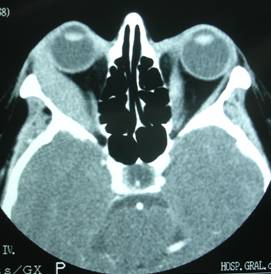

Orbital abscess

Abscesses due to cellulitis can be formed by a poorly cured or lesion formation at the subperiosteal level (near bone) caused by sinusitis. We perform radiological testing to determine the exact location because it can be formed into any wall, being more frequent in the medial and upper walls.

Treatment is surgical draining and releasing the tension of the tissues besides intense antibiotic therapy.